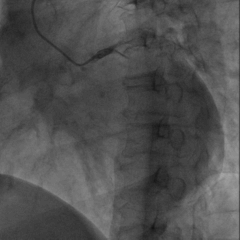

6225i球囊造影可见轻微夹层,远端未显影

6250VIS鞘管直接造影可见分支显示良好

AP

LAO